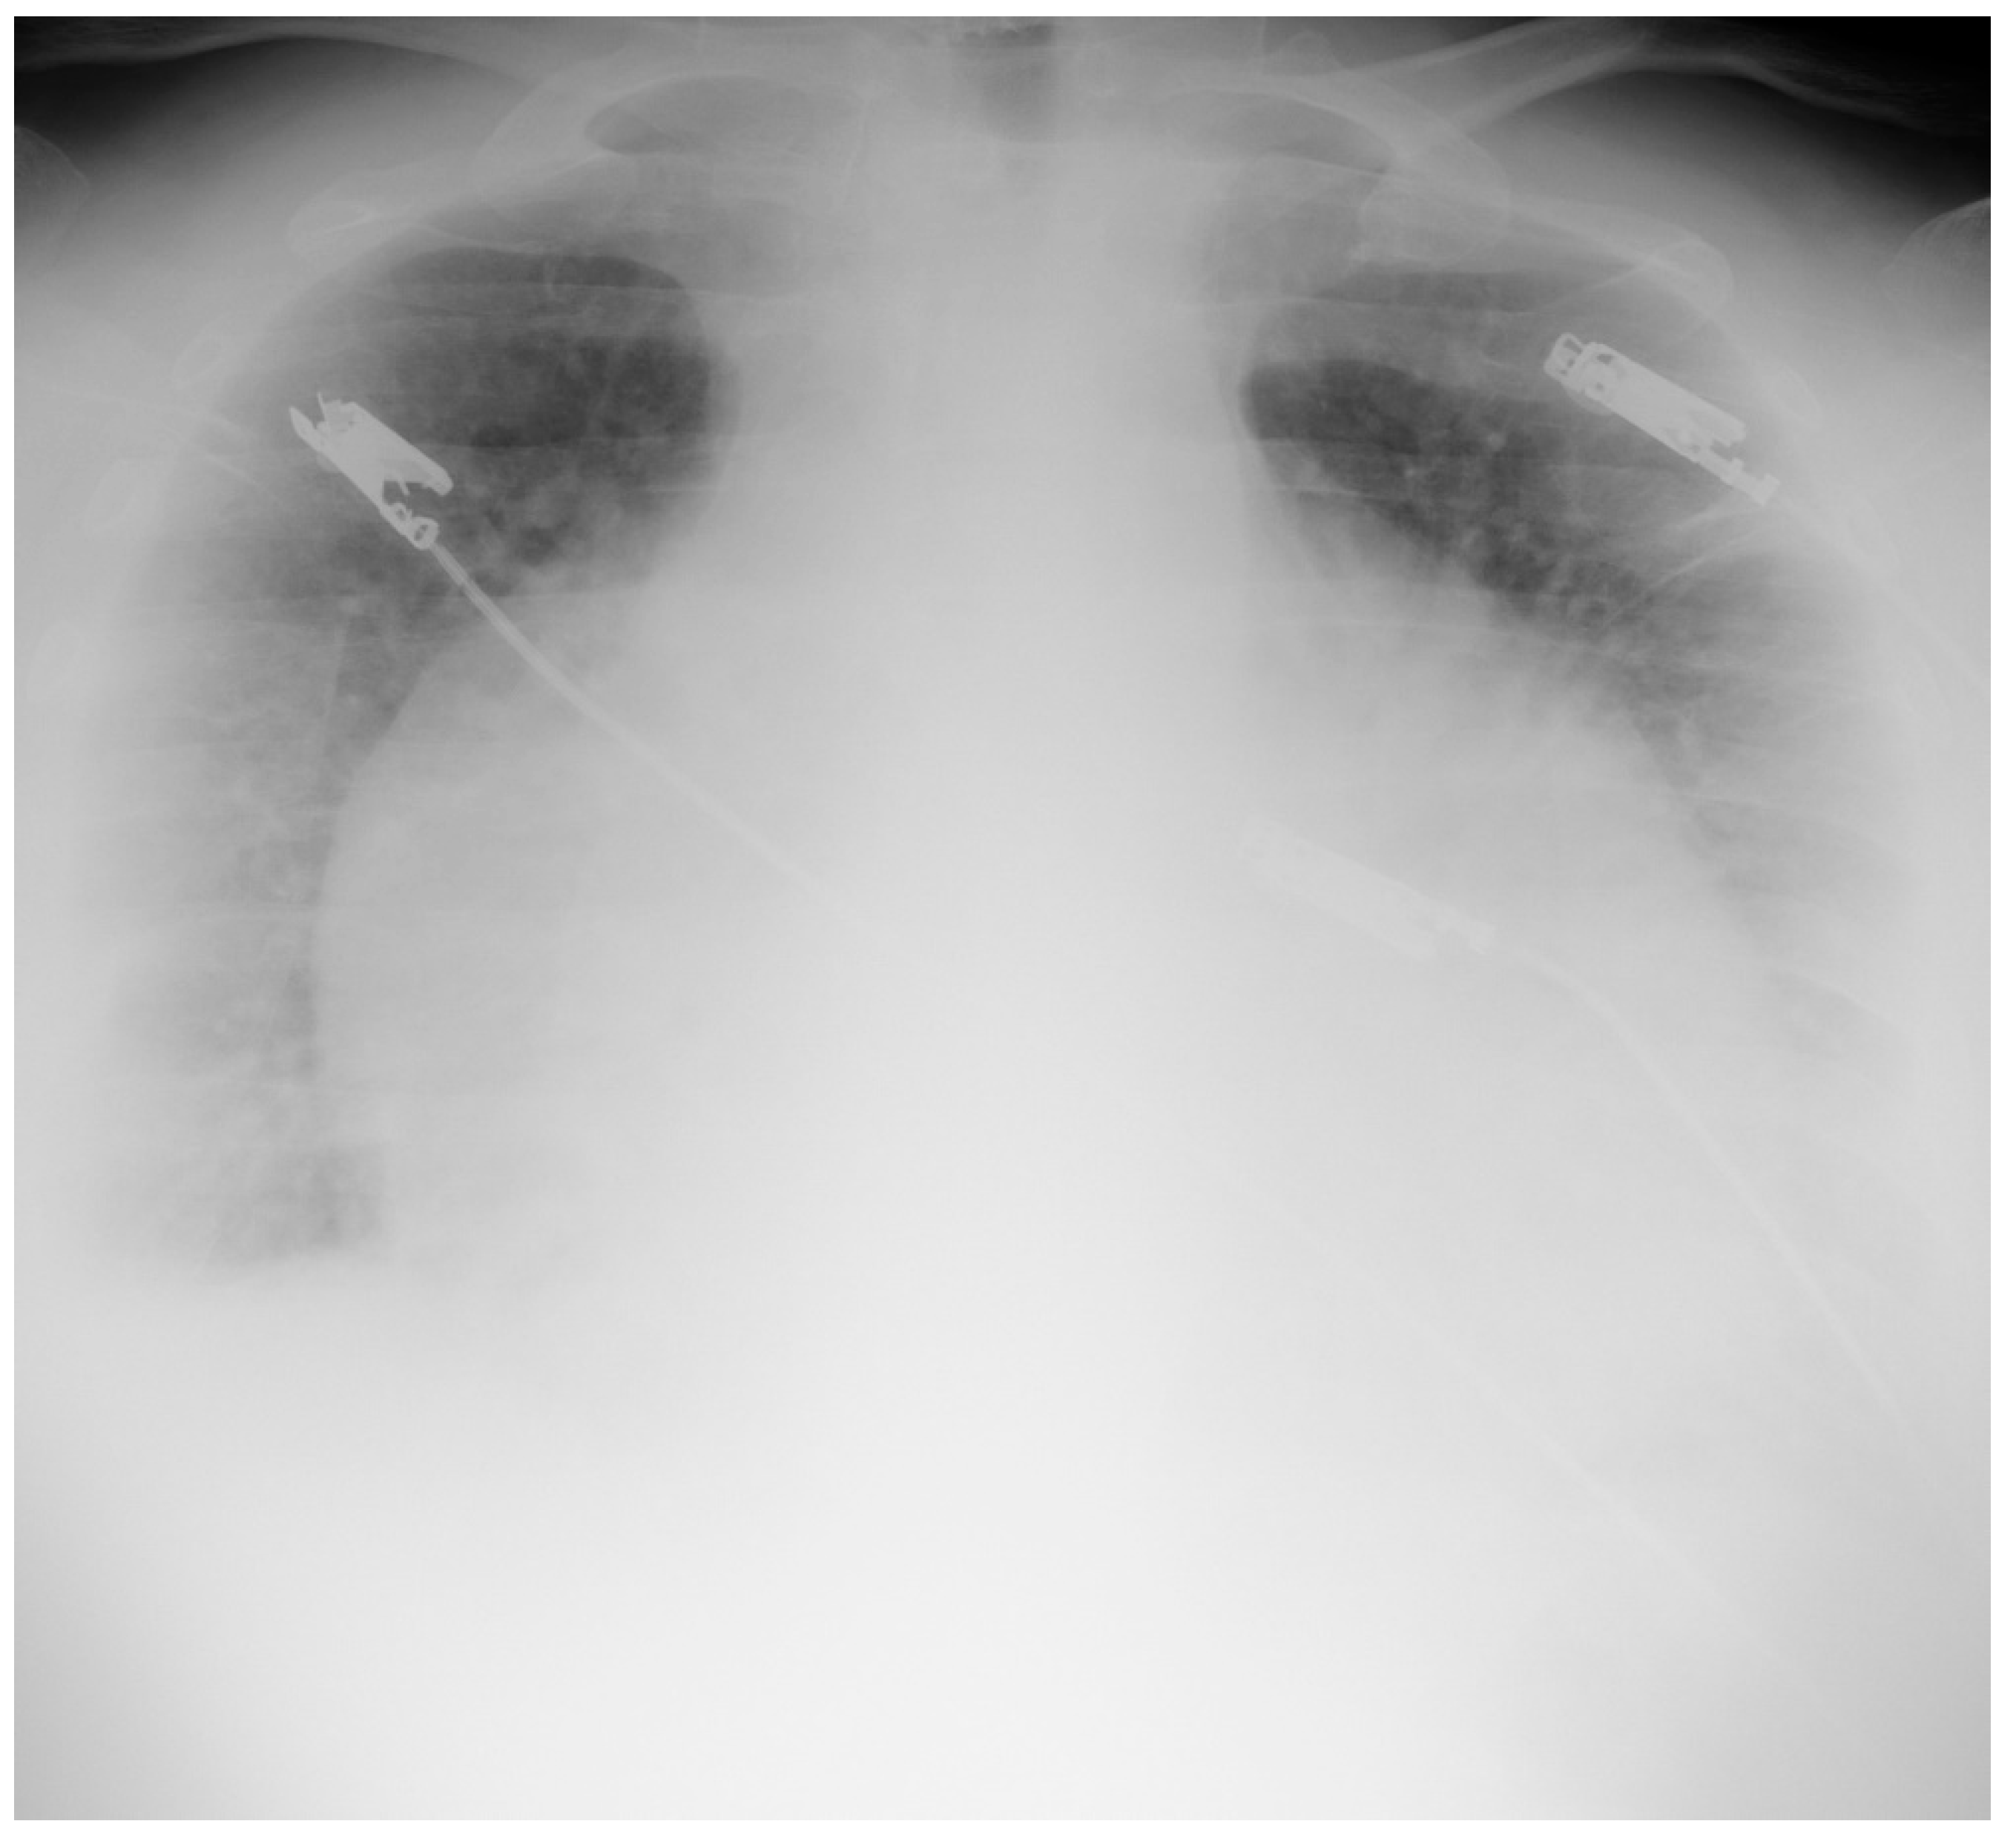

4.1.2. Chest X-ray